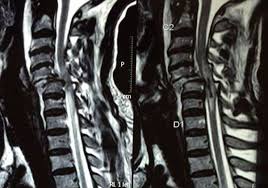

• Spinal Trauma

Level I Designation: Our facility proudly holds the official Level I Trauma Centre designation, bolstered by our in-house 24x7 Anup Blood Bank Services and state-of-the-art imaging capabilities. These include Digital X-Ray services, Computed Tomography (CT), and Magnetic Resonance Imaging (MRI) services, as well as a fully equipped laboratory.

• State of art Imaging Modalities – CT Scan services, CT Angiography Services, MRI Scan services